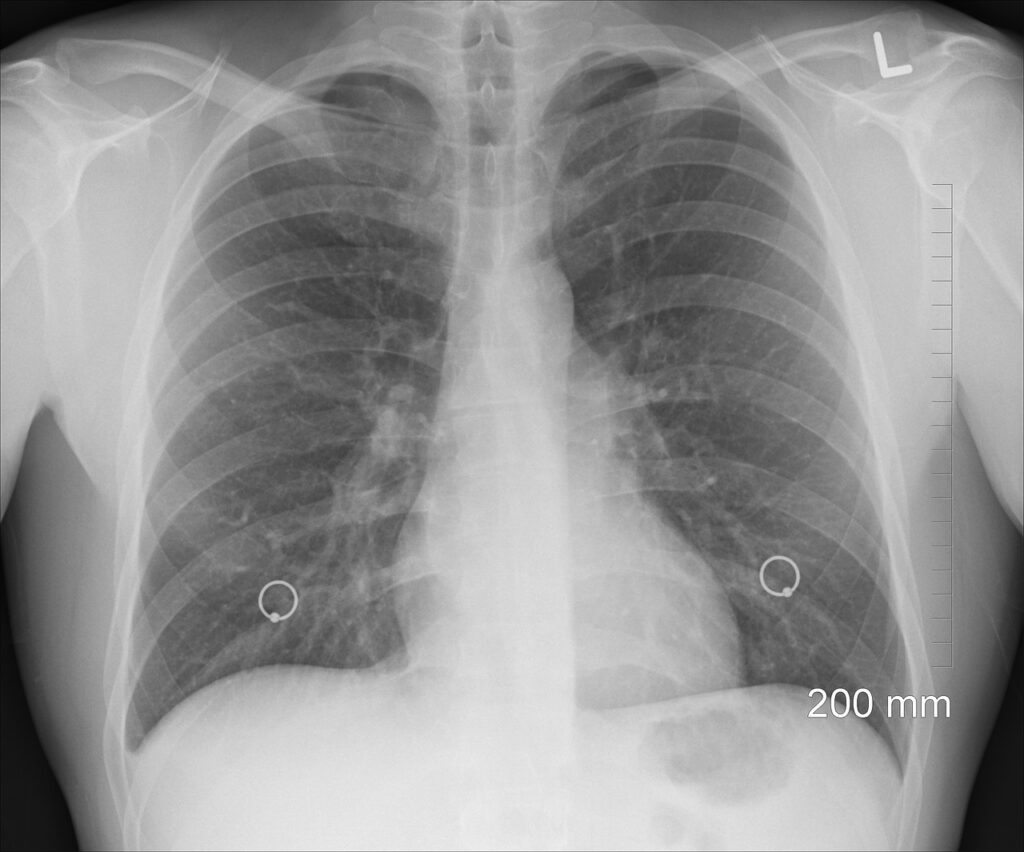

En esta línea, han trabajado en el desarrollo de un algoritmo mediante el uso de biomarcadores tumorales, con el fin de ofrecer una prueba diagnóstica económica, estandarizada, poco invasiva y accesible a cualquier laboratorio de cualquier hospital. El uso de este algoritmo ofrecería unos resultados de sensibilidad, especificidad y valores predictivos muy superiores a los obtenidos por otras pruebas. “Hemos evaluado los resultados de la aplicación de este panel de biomarcadores en diferentes hospitales y hemos realizado una validación externa de los resultados de la aplicación de este algoritmo con unos resultados muy positivos, mejores que los obtenidos por otras pruebas como las técnicas de imagen, entre otras”, subraya el Dr. Barco.

De esta forma, como asevera el Dr. Barco, el laboratorio podría participar aplicando este algoritmo de biomarcadores a los pacientes de riesgo (aquellos con historia clínica compatible con un posible cáncer de pulmón), “agilizando el posible diagnóstico y, ante un posible cribado, preseleccionando aquellos con un riesgo alto de cáncer, a los que se les realizarían las pruebas de imagen. Por lo tanto, se podría llegar a un número mayor de pacientes optimizando los recursos y ayudando a un cribado más eficiente”.